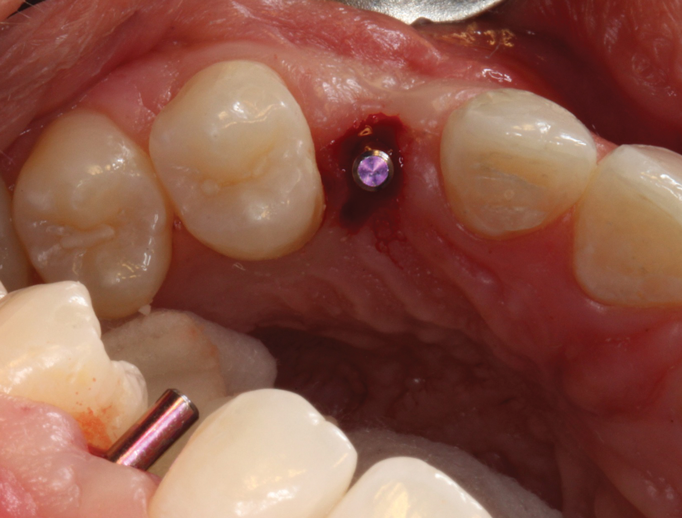

(13.) The appropriateness of the apical depth of the implant head was confirmed.

Figure 13